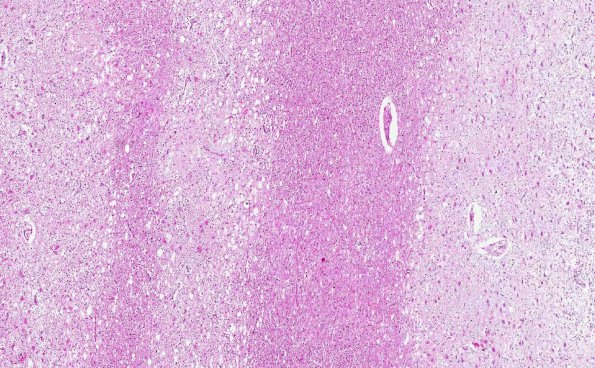

Washington University Experience | MYELIN (IMMUNE-MEDIATED) | Balo Concentric Sclerosis | 4C1 Balo Concentric Sclerosis (AANP 2015 Case 3) H&E 3.4X

This region, marked with an arrowhead in 4A1, shows a lesser degree of myelin preservation than 4B3 (H&E)